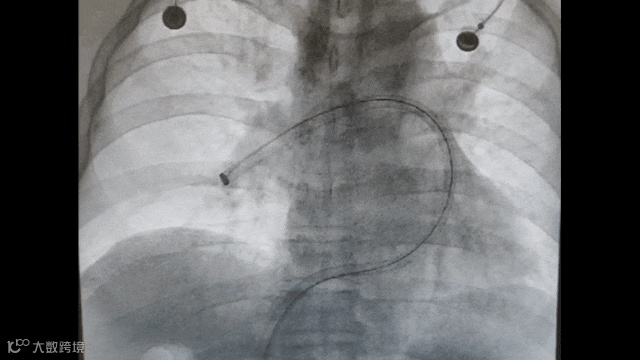

将Tendvia®血栓抽吸导管,沿导丝推送至肺动脉。管口贴近血栓处停止,撤出导管芯,进行血栓抽吸治疗。

血栓抽吸治疗